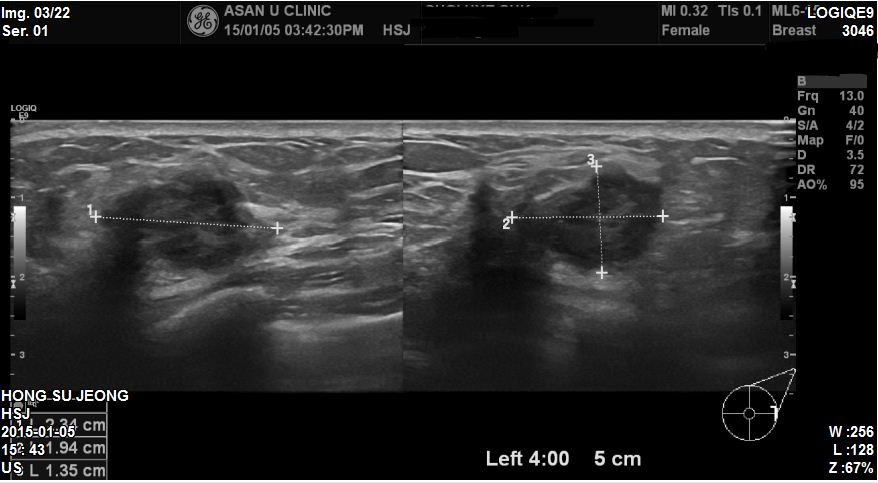

상기환자 마사지 받으시면서 발견한 혹으로 내원하신 53세 환자분이십니다.

본원에서 유방초음파 진행하였고 좌측유방 4 : 00방향에 2.3cm혹이있었고

겨드랑이 림프절도 많이 부어있었습니다.

결과상 좌측유방에 침윤성유방암 진단되었고 겨드랑이까지 전이된 상태였습니다.